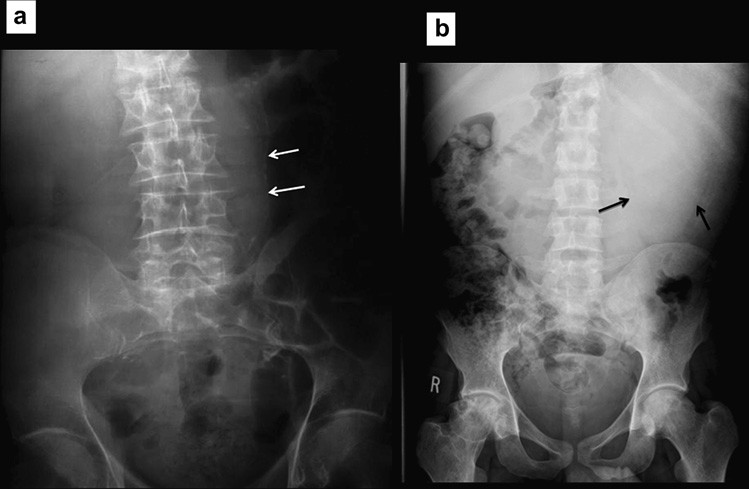

Các dấu hiệu trên phim thường quy là các quai ruột non bị giãn, đường kính trên 30 mm ở đoạn gần và trên 25 mm ở đoạn xa. Các mức khí dịch có chân rộng hơn 25mm là bất thường, các mức khí-dịch của một quai ruột ở các độ cao khác nhau (hình bậc thang) và các bóng khí bị kẹt giữa các quai ruột giãn (dấu hiệu hình tràng hạt) cũng là dấu của hiệu tắc ruột. Ít phổ biến, nếu các quai ruột bị giãn chứa đầy dịch thì phim X quang bụng cho thấy các quai ruột trong ổ bụng rất ít khí làm tăng nghi ngờ tắc ruột ở bệnh nhân có triệu chứng lâm sàng. Các dấu hiệu X quang có thể xuất hiện trước các triệu chứng lâm sàng từ 6 đến 12 giờ. Hình 1 cho thấy một vài dấu hiệu X quang của tắc ruột non.

Hình 1. Tắc ruột non. (a) Nhiều quai ruột non giãn, chứa đầy khí. Lưu ý nhiều nếp vòng theo chu vi ruột. (b) Rất ít khí do ruột non bị tắc chứa đầy dịch. (c) Phim X quang bụng chụp đứng cho thấy nhiều mức khí dịch-hình “bậc thang”.

Nguyên nhân dẫn tới tắc ruột non, đặc biệt là thoát vị, đôi khi có thể nhận ra trên phim X quang và nên được tìm kiếm một các hệ thống trong tắc ruột. Điều này yêu cầu phim X quang bụng phải bao phủ cả vùng bẹn vì đó là vị trí hay thoát vị gây tắc ruột nhất. Thoát vị bịt hoặc thoát vị rốn đôi khi tạo nên các mẫu hình khí gợi ý trên phim X quang, do đó chụp cắt lớp vi tính kéo xuống mức thấp hơn để đánh giá chi tiết (Hình 2). Tắc ruột do sỏi mật và các khối ổ bụng gây tắc ruột đôi khi cũng có thể được phát hiện.

Hình 2. Tắc ruột non do thoát vị nghẹt lỗ bịt. (a) Nhiều quai ruột non giãn. Lưu ý có một ít khí dưới dây chằng bẹn ở lỗ bẹn phải (b,c) Chụp CT cho thấy một quai ruột ở giữa cơ bịt trong và cơ bịt ngoài, xác định thoát vị bịt bên phải gây tắc ruột.